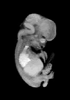

Carnegie Stage 22 (54 post-ovulatory days)

Most embryos at stage 22 are approximately 54 postovulatory days old and measure 25-27 mm in length. Distinguishing criteria for this stage include clear formation of the external ear, the hands begin to extend ventrally beyond the body wall, the fingers of one hand may overlap the fingers of the opposite hand, thickened eyelids just begin to cover the outer margins of the eye, and the superficial vascular plexus of the head now extends about three-quarters of the way above the eye-ear level.